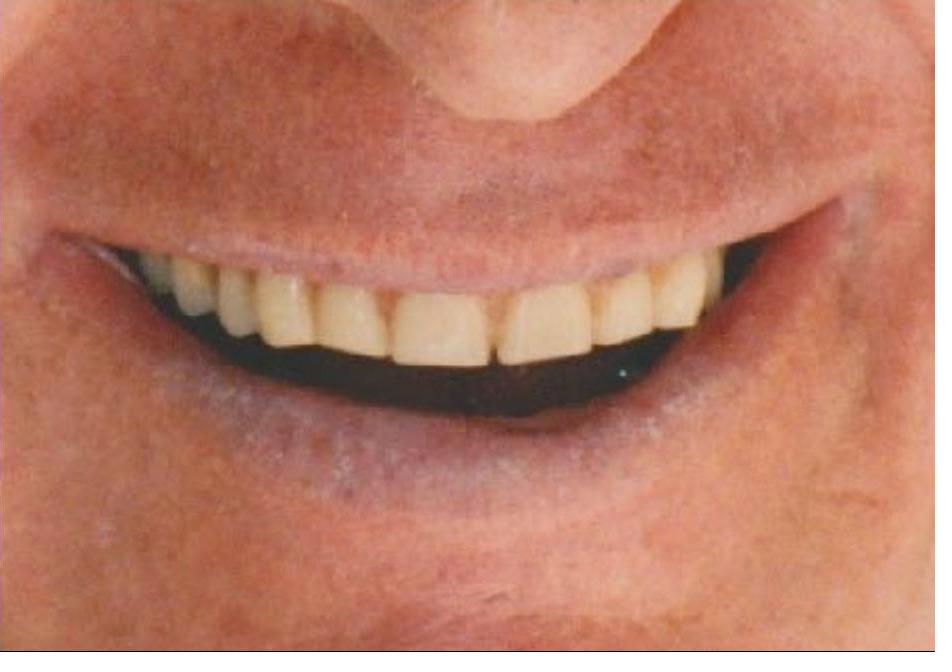

Following orthodontic treatment and periodontal crown lengthening, I fabricated 8 upper veneers for this patient. She was thrilled with her smile and the result of our interdisciplinary care.

This patient wanted a more attractive smile. Following orthodontic treatment and esthetic crown lengthening, I fabricated veneers for her upper 8 teeth. She was thrilled with the result of our interdisciplinary care and said "Oh my God, they look so good! They're gorgeous! It's so worth it!"